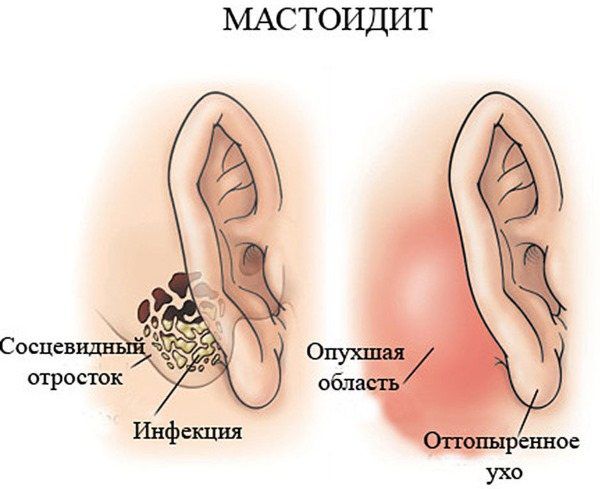

Анатомия сосцевидного отростка